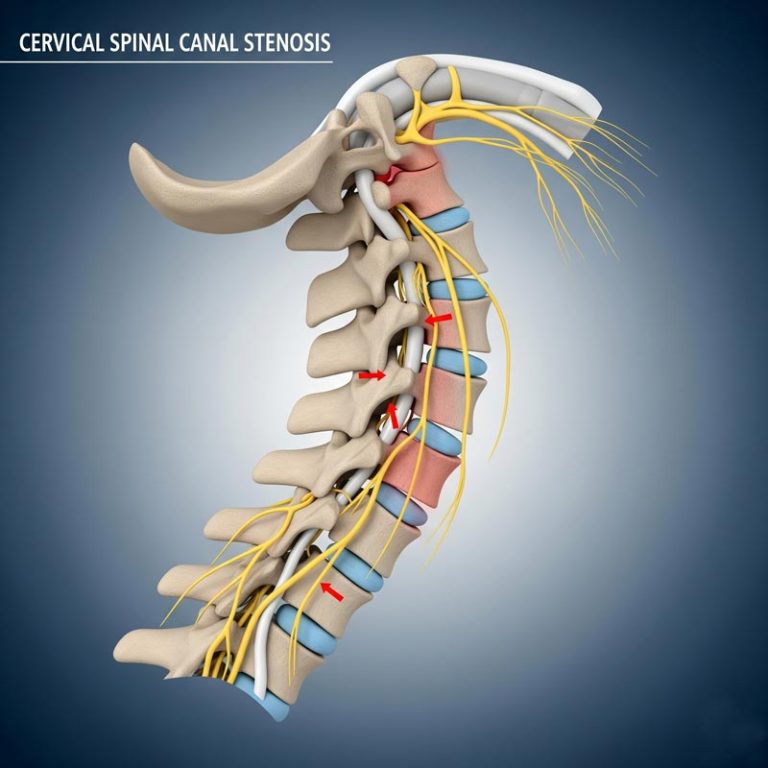

Cervical Spinal Canal Stenosis is a condition where the spinal canal in the neck narrows, putting pressure...